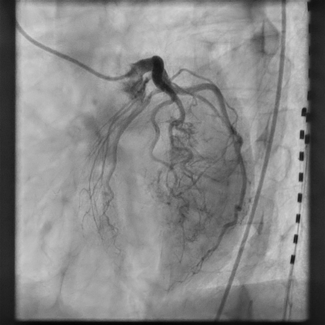

Prabhjot Hundal, MD; M. Fuad Jan, MBBS (Hons), MD; Suhail Q. Allaqaband, MD

A 77-year-old woman underwent cardiac computed tomography angiography (CCTA) for stable chest discomfort. CCTA revealed a dominant right coronary artery originating from the proximal left anterior descending artery and coursing between the...